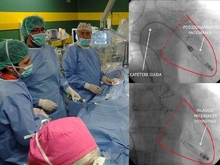

Не делая обычного для таких операций надреза в области сердца, без установки генератора импульсов под кожей грудной клетки, хирурги провели кардиостимулятор последнего поколения непосредственно к сердцу через вену в ноге пациентки. Новая технология, результат последних исследований в области нанотехнологий, позволяет избежать риска инфекции. Установка инновационных кардиостимуляторов будет проводиться в первую очередь пациентам с повышенным риском развития инфекции или с сосудистыми проблемами.